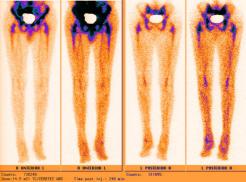

Nuclear Scan Images of Lower Torso & Lower Legs

These images were captured in order to determine why Liam’s bones broke so easily playing a video game and to also determine if there

was any Osteomyelitis. This is the diagnosis report from the scan. "There is mild increased activity noted in the lateral side of the left

ankle. However the patient does have a cast on the left leg. This uptake can be secondary to either inflammatory or infectious change within

either the skin or adjacent bone." Various contrast were used to enhance image details. The last images reminds one of the Shroud of Turin.

Hummm, makes one wonder... ;-)